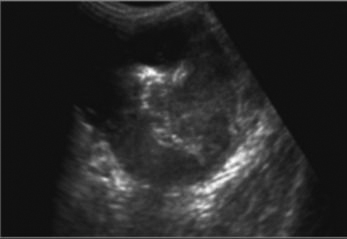

Tuberculose ileo-caecale :

Image de epaissisement circumferentiele hyperdense

de ceacum avec lymphadenopathie mesenterique (

fleche rouge ). Image

TDM en coupe coronale |

Aspect de epaissisement

et stenosant de la paroi de ileon dans tuberculose

ileo-caecale( fleche rouge ) Image TDM en coupe axiale |